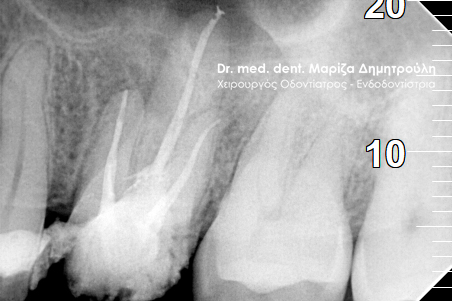

Στον ασθενή είχε πραγματοποιηθεί σε συνάδελφο ένα λευκό σφράγισμα στο αριστερό δεύτερο γομφίο της άνω γνάθου. Από τότε το δόντι εμφανίζει μέτρια (κατά διαστήματα έντονα) συμπτώματα πόνου, σε βαθμό που να μην επιτρέπει στον ασθενή να φάει με άνεση. Στην κλινική εξέταση το δόντι έδινε έντονα και ξεκάθαρα συμπτώματα πόνου στην επίκρουση. Η ακτινογραφία αποκάλυψε οτι το σφράγισμα ίσως να είχε τοποθετηθεί κοντά στο νεύρο του δοντιού, γεγονός που μπορεί να ερέθισε τον πολφό του δοντιού γι αυτό και πονούσε.

Η θεραπεία επιλογής στο συγκεκριμένο περιστατικό ήταν η απονεύρωση δοντιού. Η ενδοδοντική θεραπεία ολοκληρώθηκε σε δύο ραντεβού και το δόντι είναι πλέον ασυμπτωματικό. Η αποκατάσταση του δοντιού πραγματοποιήθηκε με λευκό σφράγισμα, εφόσον το έλλειμμα των οδοντικών ιστών δεν ήταν μεγάλο για να απαιτείται η προστασία του δοντιού με θήκη / στεφάνη.

ΠΡΙΝ

ΜΕΤΑ